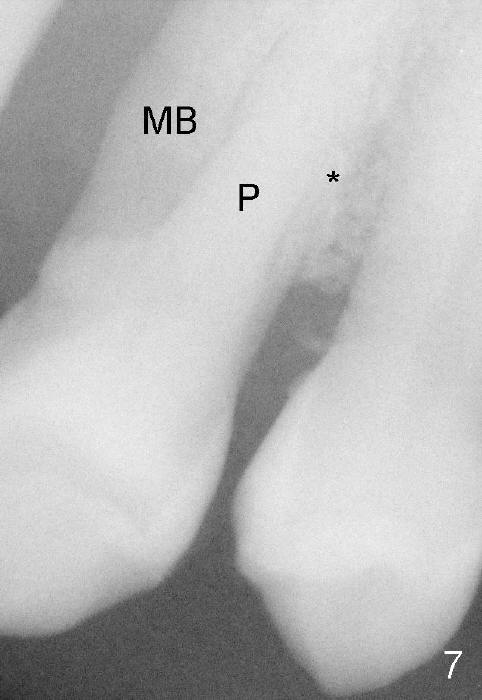

原来这个前臼齿有三个牙根(图四远中颊侧观):近中颊侧(MB),远中颊侧(DB),鄂侧(P),颊侧两个根之间有凹陷:颊侧(图五近中颊侧观:箭头),鄂侧(图六近中鄂侧观:*),凹陷处以及根分叉处充满牙槽骨,所以拔牙困难。

这种前臼齿牙根分布有点象上颌磨牙。颊侧两个根近远中宽度比鄂侧根宽(图四至图六),这个现象同样表现在X光片上(回到图一,图二),图七,图八是图一,图二放大,显示颊侧根(MB和*)比鄂侧根(P)宽,图八红线代表颊侧根根尖,黑线鄂侧根根尖。